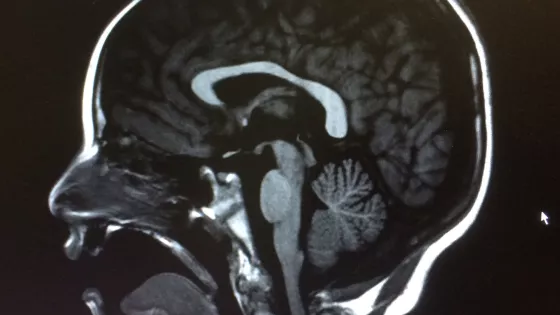

Epilepsy brains scan